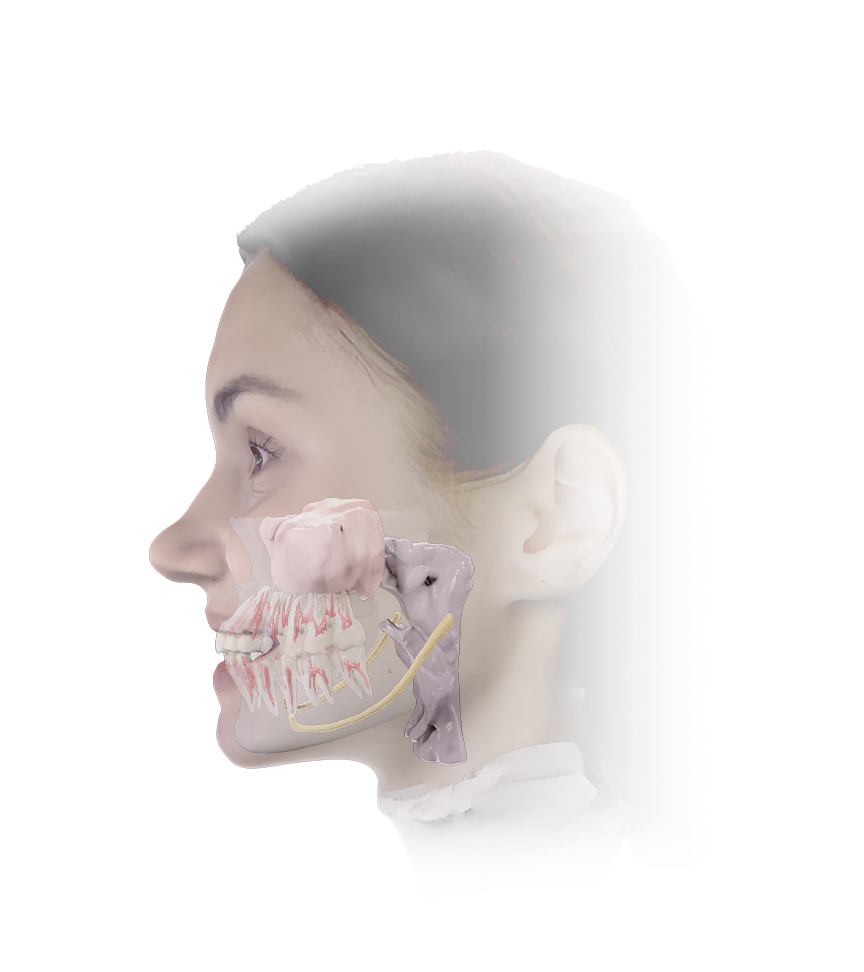

5D Solution

5D is a clinical imaging solution that combines CBCT data and facial data to create an anatomical patient model. Using intelligent technology, it automatically aligns CBCT data and segments anatomical structures to generate 5D images. This enables digital treatment and diagnosis based on accurate and intuitive data.

5D Solution

5D is a clinical imaging solution that combines CBCT data and facial data to create an anatomical patient model. Using intelligent technology, it automatically aligns CBCT data and segments anatomical structures to generate 5D images. This enables digital treatment and diagnosis based on accurate and intuitive data.